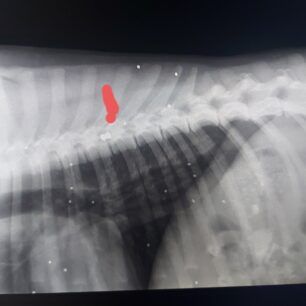

Το ζώο, όπως μας εξήγησε η κα Τσουλτσίδου, το βρήκαν ακίνητο στην είσοδο των σφαγείων. Το μάζεψαν καθώς δεν μπορούσε να κάνει ούτε βήμα και το πήγαν στην κλινική. Θεώρησαν ότι έχει χτυπηθεί από όχημα. Όμως οι ακτινογραφίες έδειξαν και τα σκάγια από κυνηγετικό όπλο, αλλά και το σφαιρίδιο του αεροβόλου, που είχε σφηνώσει κυριολεκτικά στον 8ο σπόνδυλο της σπονδυλικής στήλης του σκύλου, προκαλώντας την παραλυσία.

Η κα Τσουλτσίδου εξήγησε στο www.zoosos.gr ότι η κτηνίατρος που το εξέτασε διαπίστωσε ότι το ζώο είχε πυροβοληθεί από εξαιρετικά κοντινή απόσταση με το αεροβόλο γι’ αυτό και ο δράστης ήταν τόσο εύστοχος, καθώς κατάφερε να αφήσει παράλυτο το σκυλί που ήθελε να βασανίσει ή να δολοφονήσει.

Η κα Τσουλτσίδου στην έκκληση της μέσω facebook τονίζει τα εξής: «Ενημερωθήκαμε χτες για ένα σκύλο σε παράλυτη κατάσταση. Πιστεύοντας ότι είναι από αμάξι τον μεταφέραμε στην κτηνιατρική κλινική της κα Ζώης όπου μείναμε άναυδοι. Στοχευμένη βολή από κοντά (το σκυλί ήταν φοβικό συνεπώς ήταν κάποιος που εμπιστευόταν). Εσκεμμένα στον 8ο σπόνδυλο ώστε να βασανιστεί από τον πόνο. Ένα σκυλί σε κατάσταση σοκ να τρέμει από το φόβο. Πολλαπλές βολές μέσα του, από κάποιον που το πλησίασε, το χάιδεψε κι έπειτα το πυροβόλησε. Ένα σκυλί που δεν πείραζε κανέναν. Έχουν ενημερωθεί οι αρμόδιοι φορείς. Ντρέπομαι για τον τόπο μου. Οποιος θελει να βοηθησει δινουμε λογαριασμο κτηνιατρειου».